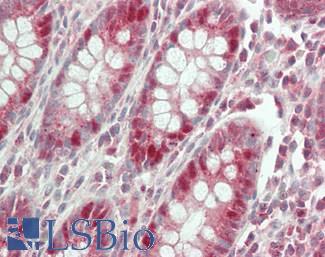

MUC2

Anti-MUC2 antibody IHC of human intestine. Immunohistochemistry of formalin-fixed, paraffin-embedded tissue after heat-induced antigen retrieval. Antibody LS-B5562 dilution 1:100.